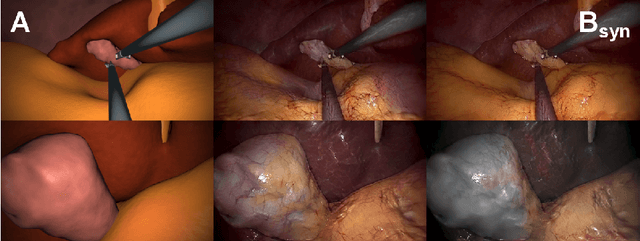

Abstract:In the medical domain, the lack of large training data sets and benchmarks is often a limiting factor for training deep neural networks. In contrast to expensive manual labeling, computer simulations can generate large and fully labeled data sets with a minimum of manual effort. However, models that are trained on simulated data usually do not translate well to real scenarios. To bridge the domain gap between simulated and real laparoscopic images, we exploit recent advances in unpaired image-to-image translation. We extent an image-to-image translation method to generate a diverse multitude of realistically looking synthetic images based on images from a simple laparoscopy simulation. By incorporating means to ensure that the image content is preserved during the translation process, we ensure that the labels given for the simulated images remain valid for their realistically looking translations. This way, we are able to generate a large, fully labeled synthetic data set of laparoscopic images with realistic appearance. We show that this data set can be used to train models for the task of liver segmentation of laparoscopic images. We achieve average dice scores of up to 0.89 in some patients without manually labeling a single laparoscopic image and show that using our synthetic data to pre-train models can greatly improve their performance. The synthetic data set will be made publicly available, fully labeled with segmentation maps, depth maps, normal maps, and positions of tools and camera (http://opencas.dkfz.de/image2image).